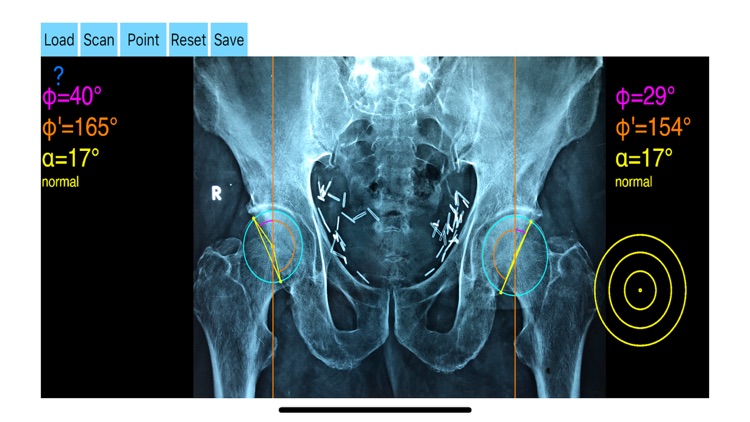

AcetabularAnteversionApp screenshot-3

Acetabular version is conventionally evaluated on CT scans but excessive radiation doses associated with routine use of computed tomography (CT). An objective radiographic tool which provides measurements comparable in accuracy to CT measurements has been developed by Dr. Hefti (Nomogram).Tedious and time-consuming calculation has to be done in simple X-rays in order to calculate the acetabular anteversion. The primary goal of this App is to help determine radiographic values of acetabular anteversion in a practice in a blink of an eye and avoiding CT scans.

-By marking certain points in a simple standard AP pelvic radiograph, geometric parameters are being calculated. The App computes the acetabular anteversion based on a pelvic AP radiograph. The angle of anteversion is calculated through the formula according to Heftis nomogram. The acetabular orientation (anteversion/retroversion) is determine by the app by the measurement of the angles between the center of the femoral head and the anterior (φ) and posterior (φ’) acetabular rim.

Once you choose correctly the anterior and posterior acetabular rims the app calculates the acetabular anteversion based on nomogram.

-The data are printed over to screen so each case can easily assessed